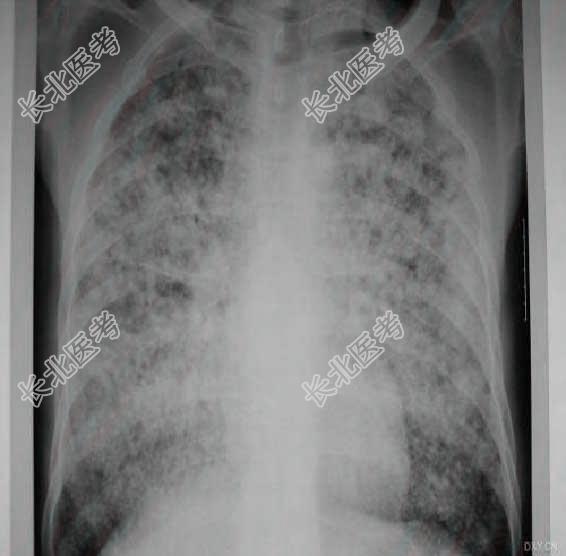

- [材料题] 患者男性,47岁,8天前受凉后出现发热,午后较高,最高41℃,无畏寒,感胸闷,偶有干咳,无咯血。当地胸片示:两肺弥漫小结节影。痰找抗酸杆菌3次(-),PPD阴性,血TB-MYCODOT(+)。当地给予静滴先锋5和先锋铋3天热未退。曾患血吸虫病,无肝炎.糖尿病与肺结核病史,采石30年。查体:T39.8℃,P102次/分,R20次/分,BP120/80mmHg,消瘦,两肺呼吸音粗,未闻及干湿罗音。入院血象:WBC10.2×10⁹/L,N0.947,L0.04,RBC4.05×10¹²/L。

- 多项选择题1.提示:6月2日胸片(入院时胸片),见下图。

- 多项选择题3.提示:根据病史和X线影像。见下图。

首先考虑哪些诊断 A、粟粒性肺结核

B、肺泡细胞癌

C、外源性过敏性肺泡炎

D、AIP(急性间质性肺炎)

E、NSIP(非特异性间质性肺炎)

F、ARDS(急性呼吸窘迫综合征)

G、尘肺